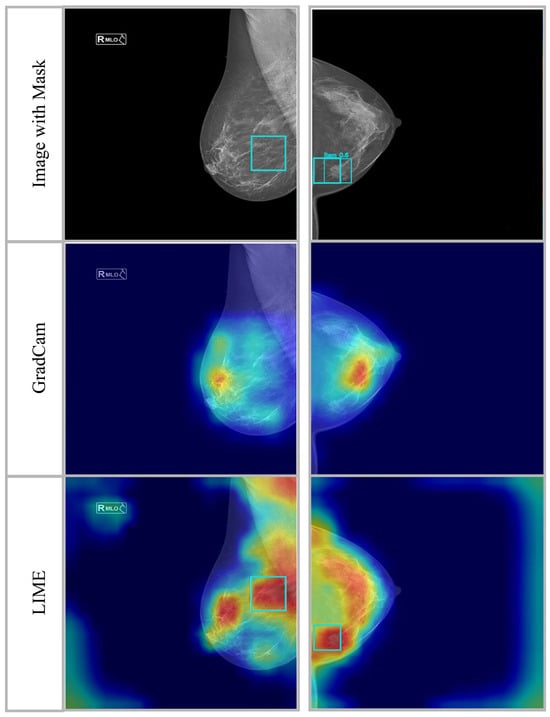

Figure 11 shows how well Grad-CAM and LIME, two popular explainability methods, extract and optimize the proposed model’s features. The first row (Image with Mask) shows the original mammographic pictures with bounding boxes emphasizing ground truth lesion spots. The categorization technique identified these sites as potentially cancerous or suspicious. The model’s feature activation zones are visualized using Gradient-weighted Class Activation Mapping in the second row. This method reveals the model’s spatial importance by highlighting the categorization decision’s most important locations. Warm colors (yellow and red) over lesion sites suggest that the 32-layer CNN model, improved with mGWO for feature optimization, correctly concentrates on key mammographic regions, exhibiting its good localization capabilities. Third row (LIME visualization) validates model interpretability and feature importance with Local Interpretable Model-Agnostic Explanations (LIMEs). A LIME generates local explanations by perturbing input pixels and detecting classification effects, unlike Grad-CAM, which provides global feature importance. LIME maps show red and orange regions, confirming that the model effectively identifies vital areas while minimizing irrelevant feature extraction. This shows that mGWO feature selection reduces redundancy and improves discriminative feature learning.

Figure 11.

Activation heatmaps superimposed on mammography images to illustrate the network’s areas of concentration for benign and malignant classifications. Areas depicted in red signify greater model attention, whilst cooler hues imply less pertinent locations. These maps are utilized to evaluate the interpretability and dependability of the deep learning model.